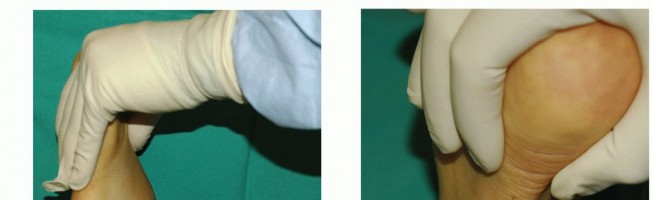

During the physical examination, the surgeon must assess the flexibility of the hindfoot. The single-leg heel rise test is a critical diagnostic maneuver; inability to perform this test or failure of the hindfoot to invert during heel rise indicates significant PTT insufficiency.

In cases of persistent tenosynovitis, patients will exhibit marked fullness behind the medial malleolus. This swelling is often unresponsive to prolonged immobilization.

FIGURE 82-19 A, Persistent posterior tibial tenosynovitis on the left was unresponsive to many weeks of casting and several months of double upright brace wear with a medial T-strap. Note the fullness behind the medial malleolus on the left, not seen on the right.

FIGURE 82-19 B, Closer view of the medial aspect of the left ankle showing the distinct area of tenosynovitis.